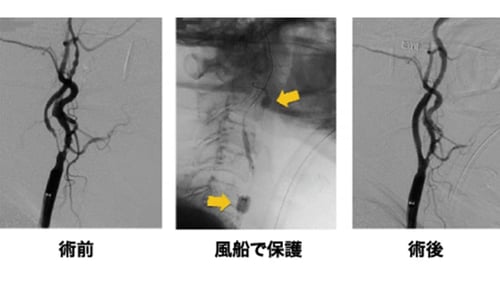

頸動脈ステント留置術は、主に足の付け根の血管(大腿動脈)からカテーテルを通して、頸動脈の狭窄部分に“ステント”と呼ばれる金属製の網状の筒を留置して、血管を正常径まで拡張させる血管内手術です。血管を拡張させる時に、コレステロールの破片や血栓が脳内に流れて行くと脳梗塞を生じてしまいますので、 その予防のために小さなフィルターや風船をあらかじめ狭窄部位の先に進めておいて、治療中にコレステロールの破片や血栓が脳に飛ばないようにして脳梗塞を防ぎます(図5)(図6)。

治療時間は通常1~2時間程度です。この治療は、直達手術の内膜剥離術と比較して体の負担が少なく、高齢者やさまざまな合併症を持った方にも行うことができます。入院期間は1週間ほどです。